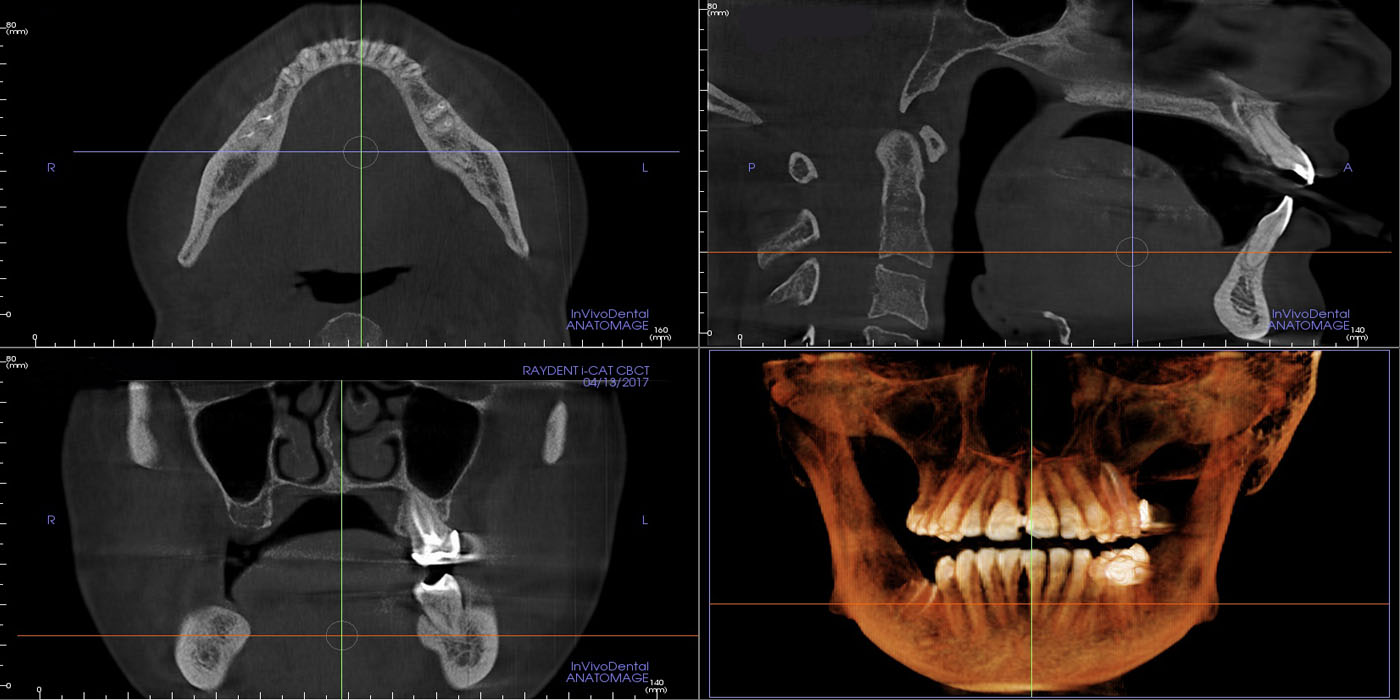

Dental cone beam computed tomography (CT) is a special type of x-ray equipment used when regular dental or facial x-rays are not sufficient. this technology produces three dimensional (3-D) images of teeth, soft tissues, nerve pathways and bone in a single scan.

Dental cone beam CT is commonly used for treatment planning of orthodontic issues. It is also useful for more complex cases that involve:

• Surgical planning for impacted teeth.

• Diagnosing temporomandibular joint disorder (TMJ).

• Accurate placement of dental implants.

• Evaluation of the jaw, sinuses, nerve canals and nasal cavity.

• Detecting, measuring and treating jaw tumors.

• Determining bone structure and tooth orientation.

• Locating the origin of pain or pathology.

• Cephalometric analysis.

• Reconstructive surgery.